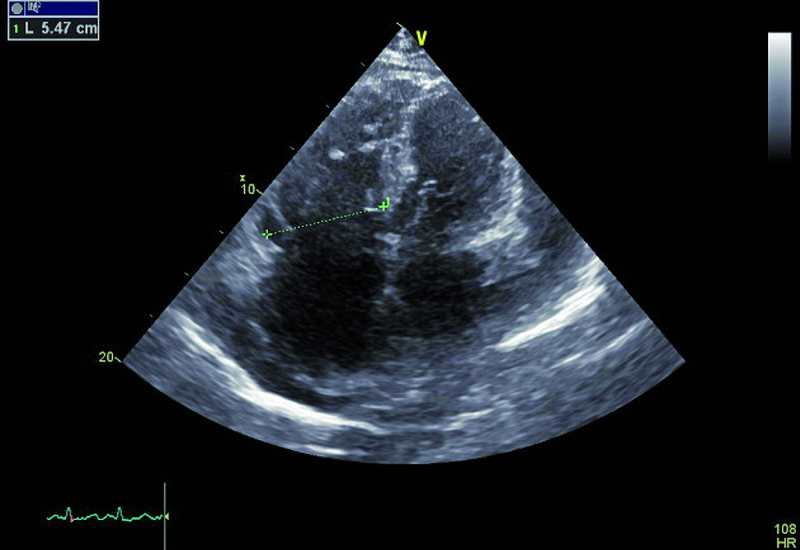

Kobieta, lat 73. Jakie patologie można rozpoznać na rycinach?

3. Powiększenie jamy prawej komory (ryc. 2).

4. Płyn w jamie osierdzia (ryc. 2).